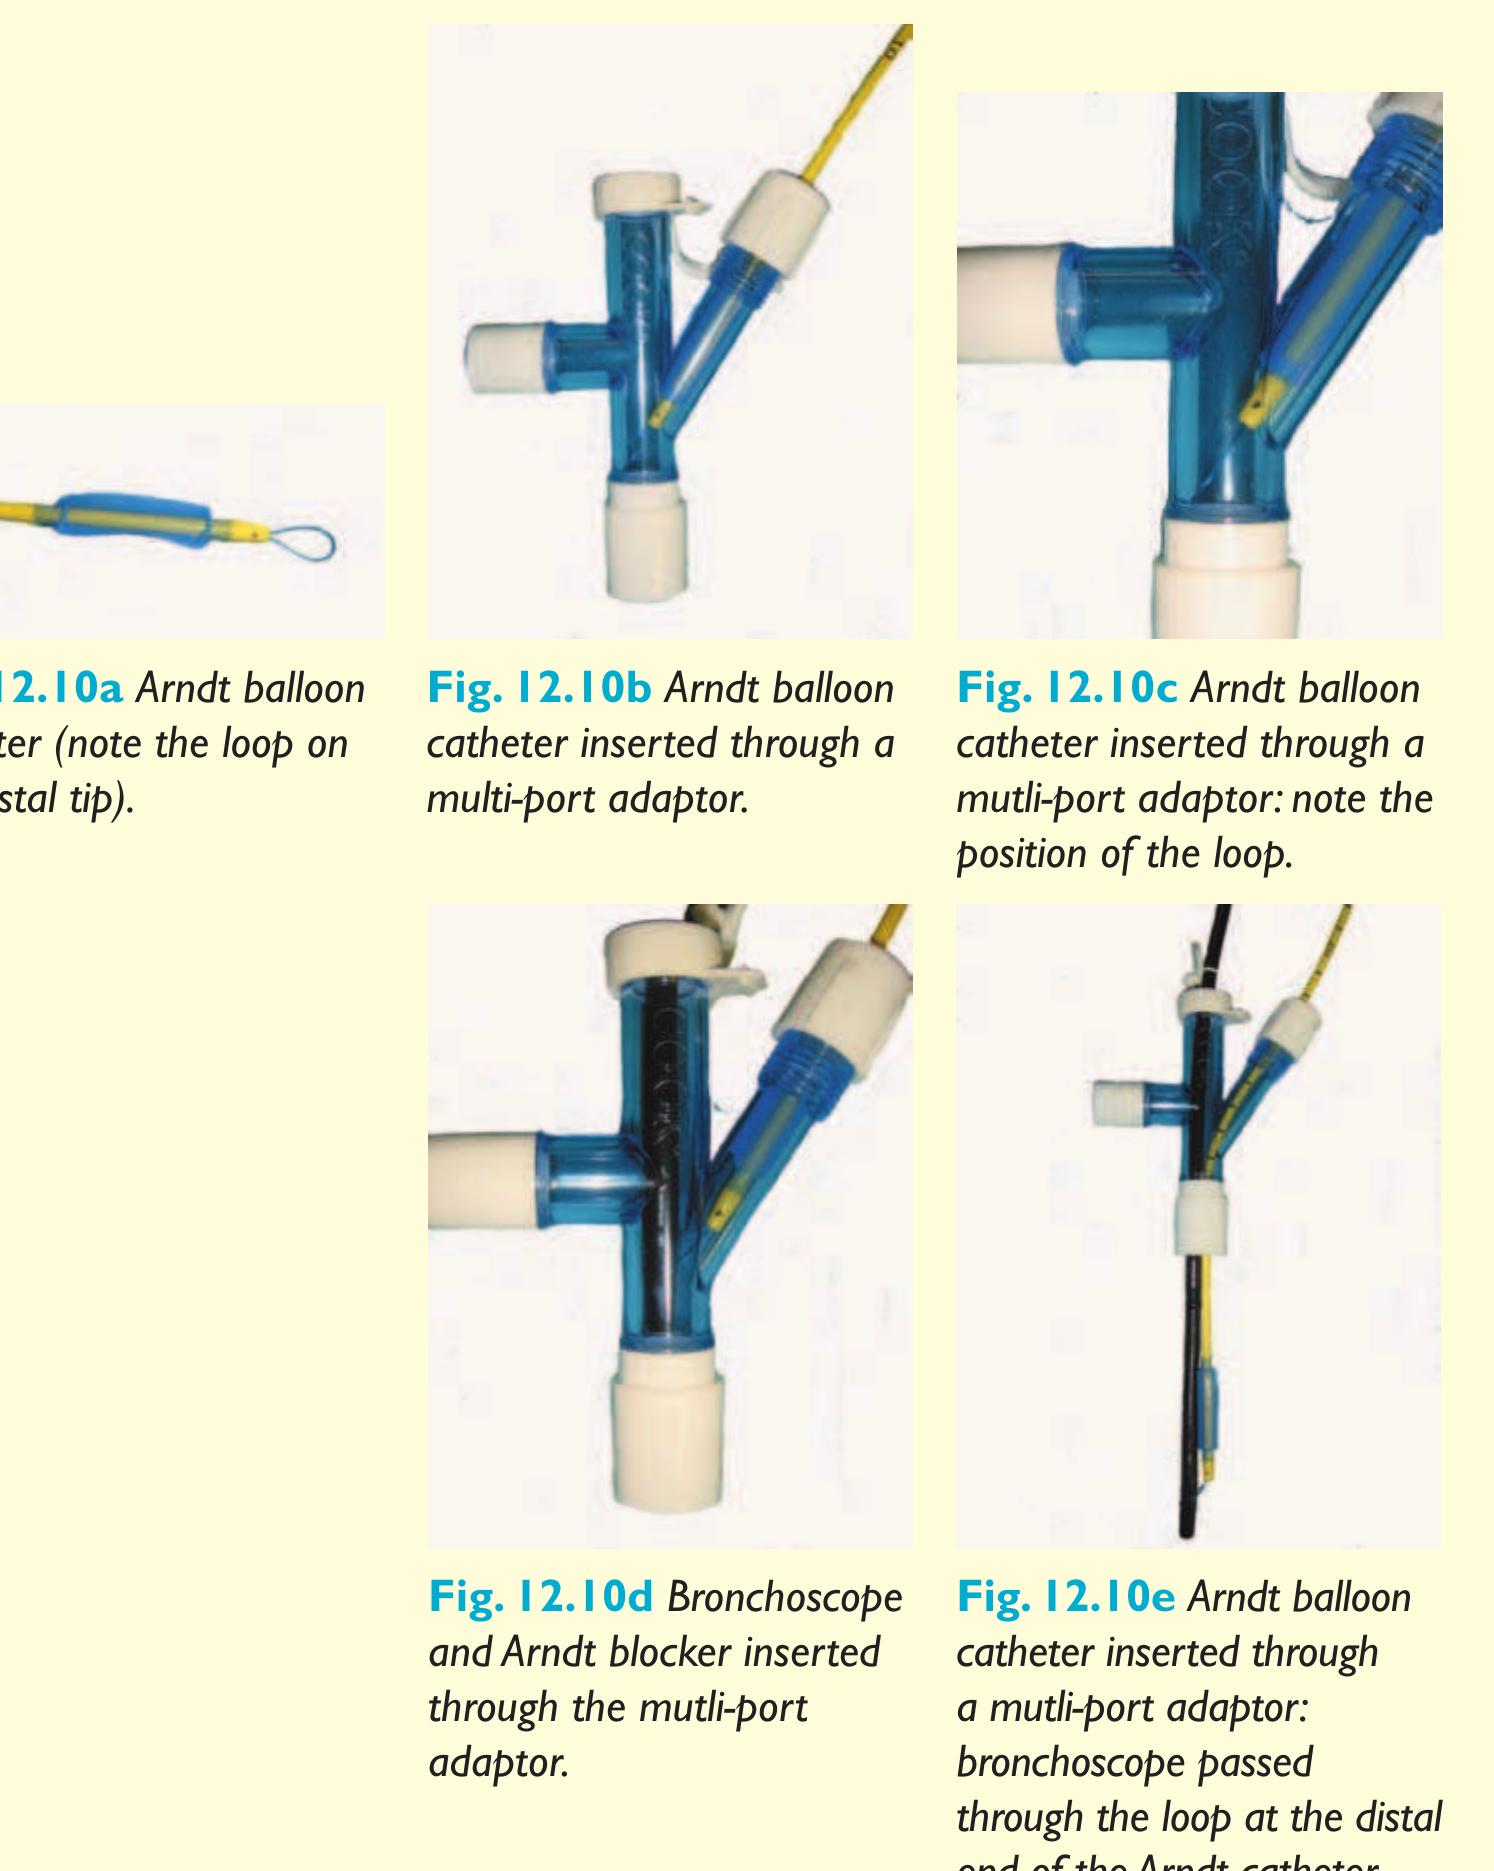

- Once the loop is tightened around the bronchoscope, the endobronchial blocker can be guided to any lobar bronchus (Fig. 12.11).

- Bronchoscopy with the nasal approach is performed and a polyethylene catheter is placed through the instrument channel of the bronchoscope and into the desired airway.